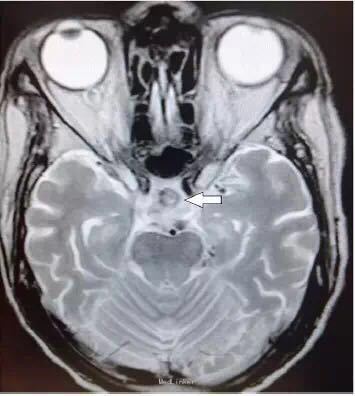

男性患者,82 岁,主因突发双眼复视和头痛就诊,既往有垂体大腺瘤病史。

体格检查显示双眼完全性上睑下垂。双侧动眼神经麻痹,右侧外展神经麻痹,水平性前庭 - 眼反射受损,瞳孔反射受损。视野和肌力检查正常。 血清钠为 112 mmol/L(正常值为 136-145 mmol/L);清晨皮质醇水平为 57 nmol/L(正常值为 171-536nmol/L)。甲状腺功能检查正常。

紧急行经蝶入路的垂体肿瘤全切术。在手术后动眼神经麻痹的症状有部分缓解。

表现为双侧动眼神经麻痹的垂体卒中十分罕见。垂体卒中是一种潜在威胁生命的疾病,以突发头痛、视力障碍、眼肌麻痹以及意识障碍为主要特征。垂体卒中是由垂体出血或梗死所致,大约 2/3 的患者伴有急性继发性肾上腺功能不足,这也是死亡的主要原因之一。